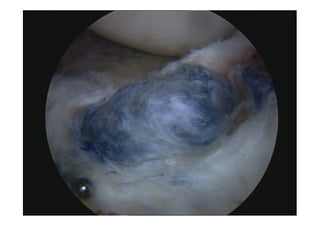

El ojo de la

cerradura